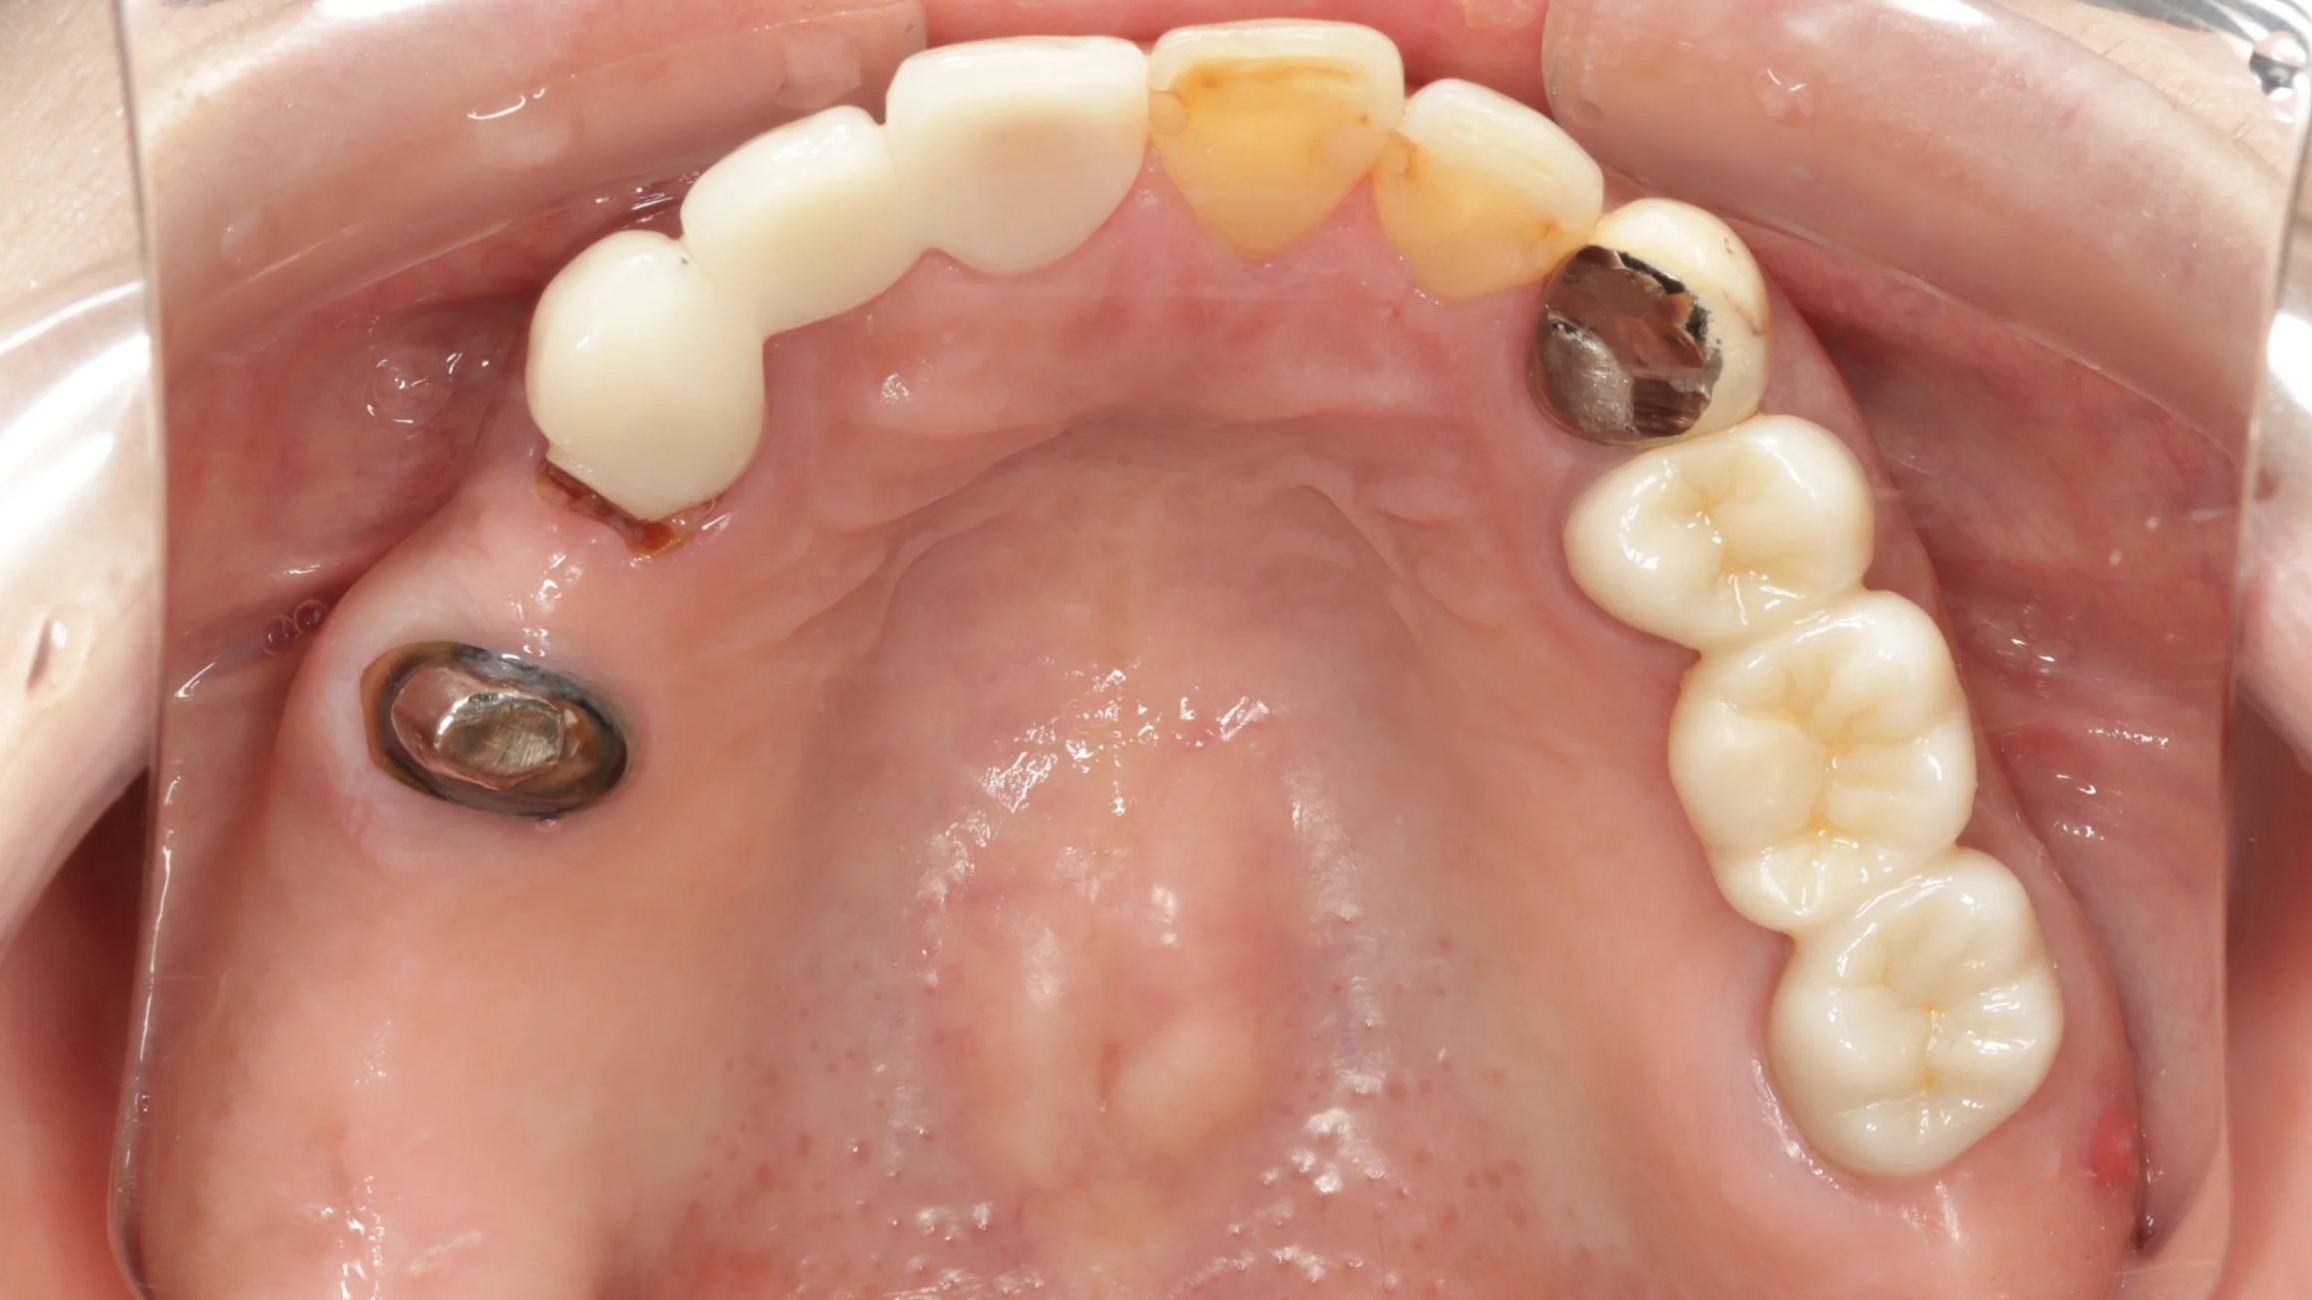

初診時

大きなむし歯もある状態でしたがまずは、入れ歯を早期に装着し、入れ歯の調整をしつつ、歯の治療することとしました。

2回目

残せる歯は、しっかり根の治療を開始しつつ、新しい入れ歯を装着。内側を金属で薄く作る事で違和感の軽減を図りました。